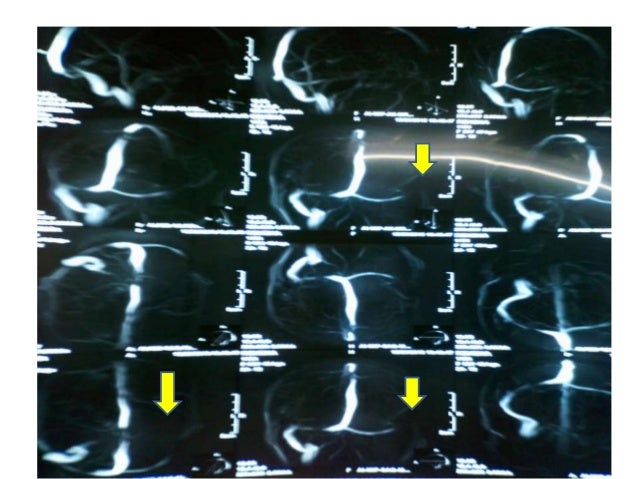

Cerebral Venous Sinus Thrombosis (CVST) Case Report

Residents and fellows contest rules | international ophthalmologists contest rules. Severe dehydration after competitive sport had induced cvst. Background and purpose—in cerebral venous thrombosis (cvt), the sensitivity of conventional mri sequences to detect clot in the sinuses or veins is incomplete and largely depends on the time elapsed since thrombus formation. H u h n a. The superior sagittal sinus and lateral sinuses were identified as the most commonly affected sinuses.

Cerebral venous sinus thrombosis occurs when a blood clot forms in the brain's venous sinuses.